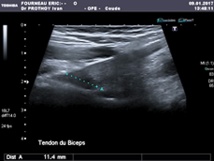

L'échographie retrouve un épaississement hypoéchogène de l'insertion basse du tendon. Une IRM confirmera le diagnostic.